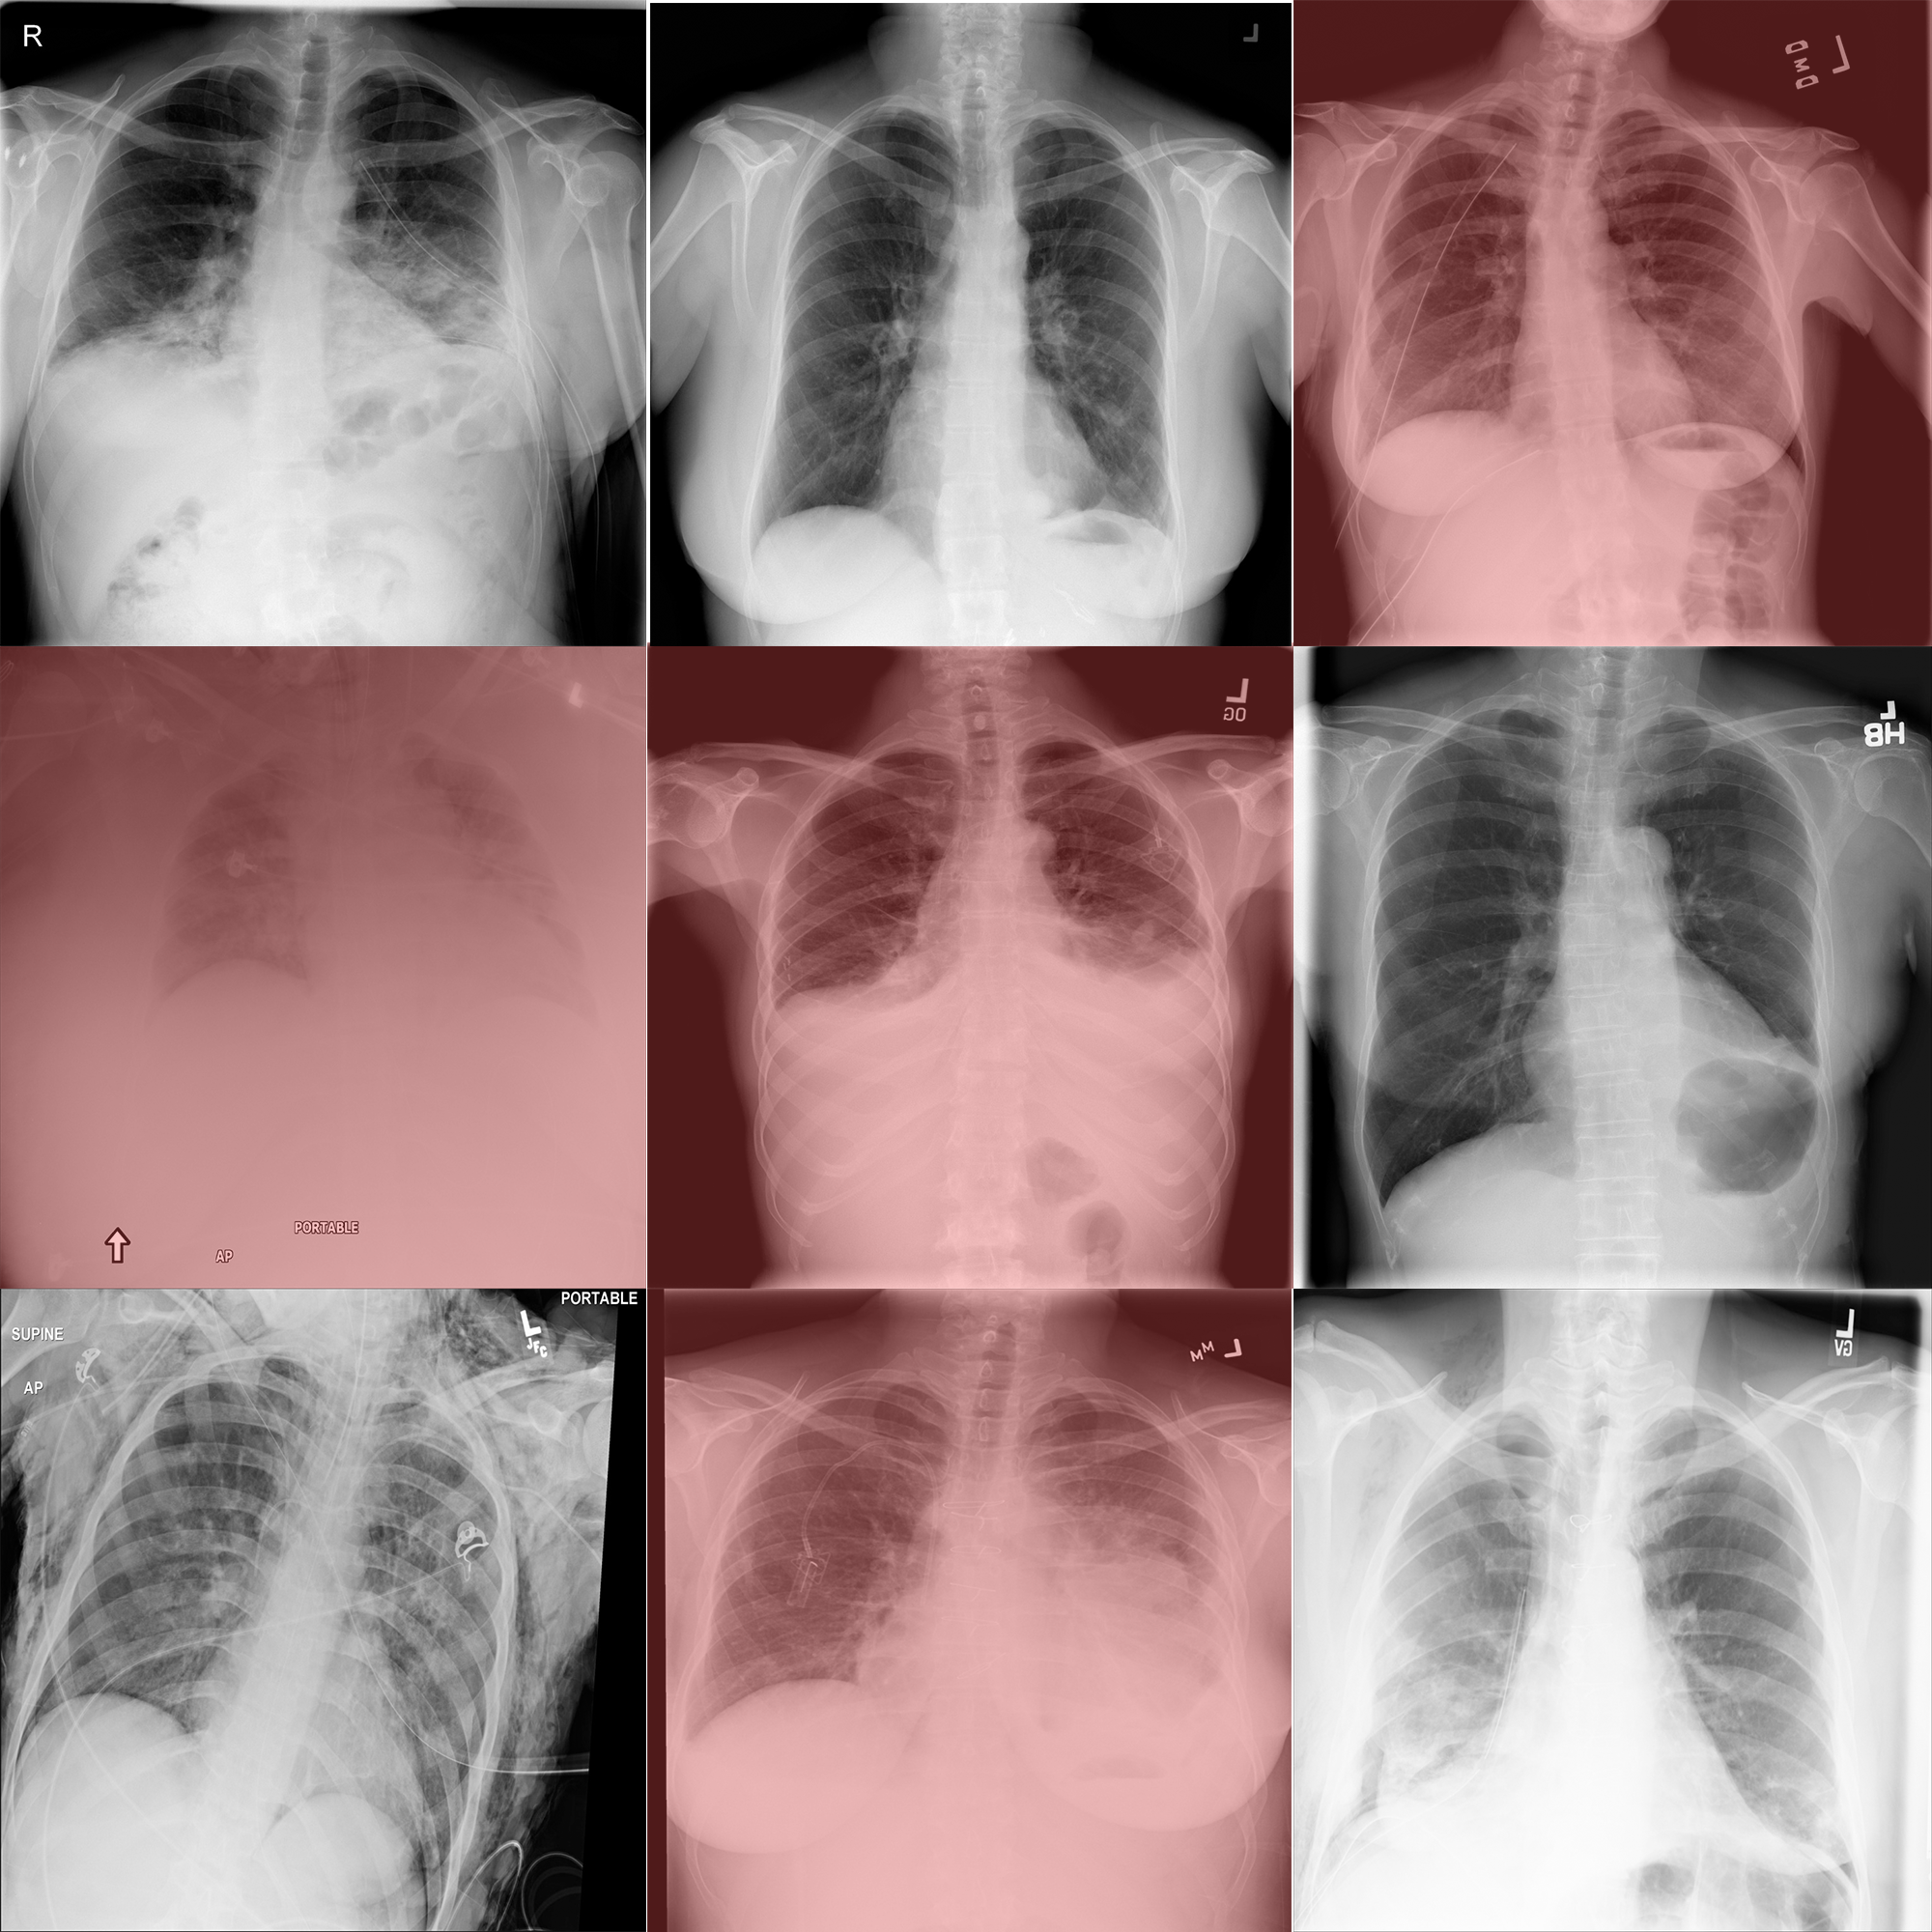

Let's train a binary classifier that can distinguish people with or without Pneumothorax thanks to their radiography.